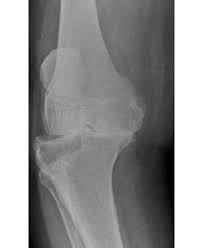

Ingwer ist in der Lage ein bestimmtes Enzym im Körper zu hemmen das bei Arthrose Schmerzen hervorrufen kann. Arthrose tritt allerdings immer häufiger bei jungen Menschen auf. AndreyPopov iStock Als Kniearthrose Gonarthrose bezeichnet man den fortschreitenden Gelenkverschleiß im Kniegelenk. Dabei kommen Physiotherapie physikalische Behandlungen wie unter anderem. Das Ziel der Behandlung mit Medikamenten ist es die Symptome der Kniegelenksarthrose zu beseitigen. Sie sind in Form. Viele Studien belegen dass gezielte Bewegung und Kräftigung sowohl die Muskulatur stärkt als auch die Gelenkfunktion verbessert und das Wohlbefinden steigert. Stimmt zwischen ihnen die Balance. Pharmakologische Behandlung bei Kniearthrose Hilfe aus der Apotheke.

Physiotherapie und Sport verbessern die Gelenkfunktion und reduzieren chronisch e Schmerzen bei Kniearthrose. Unser Körper muss viel aushalten. Das Ziel der Behandlung mit Medikamenten ist es die Symptome der Kniegelenksarthrose zu beseitigen. Konservative Behandlung der Kniearthrose Behandlung der Arthrose-Ursachen ist erfolgversprechender als die Therapie der Beschwerden. In der Bildergalerie finden Sie die 10 besten Tipps für gesunde Gelenke Foto. Beim Treppensteigen so viel Gewicht wie möglich auf dem Treppengeländer abstützen. Muskeln stabilisieren das Knie.